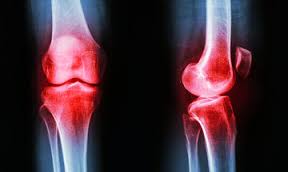

Γράφει ο Αδάμ Αθανάσιος, MD, FICS, Ορθοπαιδικός Χειρουργός- Συνεργάτης Euromedica Γενικής Κλινικής Θεσσαλονίκης Τηλ: 6974108266, 2310895191 Το γόνατο είναι η μεγαλύτερη άρθρωση του σώματος. Ο χόνδρος που βρίσκεται στο εσωτερικό, Read More…

Γράφει ο Αδάμ Αθανάσιος, MD, FICS Ορθοπαιδικός Χειρουργός, Συνεργάτης Euromedica Γενικής Κλινικής Θεσσαλονίκης Τηλ: 6974108266 Τι είναι η ρήξη μηνίσκου; Οι μηνίσκοι στο γόνατο είναι δύο: ο έσω και ο Read More…

Οι πόνοι στα γόνατα είναι αρκετά συνηθισμένοι, ιδιαίτερα σε άτομα προχωρημένης ηλικίας. Οι αιτίες που τους προκαλούν είναι πολλές με συχνότερη τις αρθρίτιδες. Οι τρεις μορφές αρθρίτιδας που επηρεάζουν τα Read More…